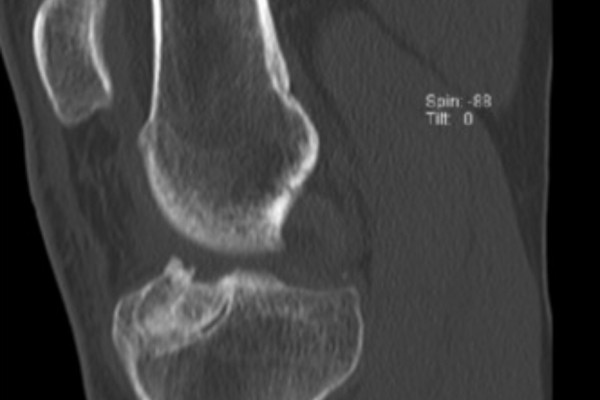

Auffüllung geweiteter Bohrkanäle mittels Spender- oder Eigenknochen

Kommt es nach einer Kreuzbandplastik zu einer erneuten Instabilität des Kniegelenkes ist häufig eine nicht ganz optimale Position der ursprünglichen Bohrkanäle oder eine Weitung der Kanäle im Laufe der Zeit die Ursache. In diesen Fällen müssen die Bohrkanäle zunächst aufgefüllt werden um die sichere Anlage, neuer Bohrkanäle zu ermöglichen. Hierfür wird zunächst das alte Transplantat im Rahmen einer Kniegelenksspiegelung aus den Bohrkanälen entfernt und die Kanäle ausgebohrt. Zur Auffüllung der Kanäle wird in der Regel Spenderknochen verwendet. Im Gegensatz zu künstlichem Material führt dieser innerhalb von 3 Monaten zu einer optimalen Durchbauung. Die Gefahr einer Abstoßung oder einer Infektion kann durch die Behandlung des Knochens vor der Implantation annähernd ausgeschlossen werden.

Die Einheilung des Knochens wird 3 Monate nach der Implantation mittels eines CTs überprüft. Anschließend kann in einem zweiten Eingriff eine erneute Kreuzbandrekonstruktion durchgeführt werden.